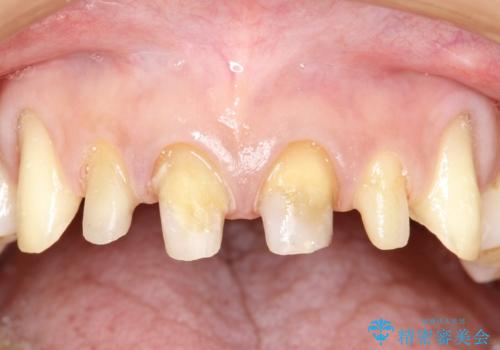

ご自身の歯とかぶせ物の境目が露出しておりました。

また犬歯の形も気になるとのことでした。

以前に装着されていたものは全て連結されており、清掃性があまり良くありませんでした。